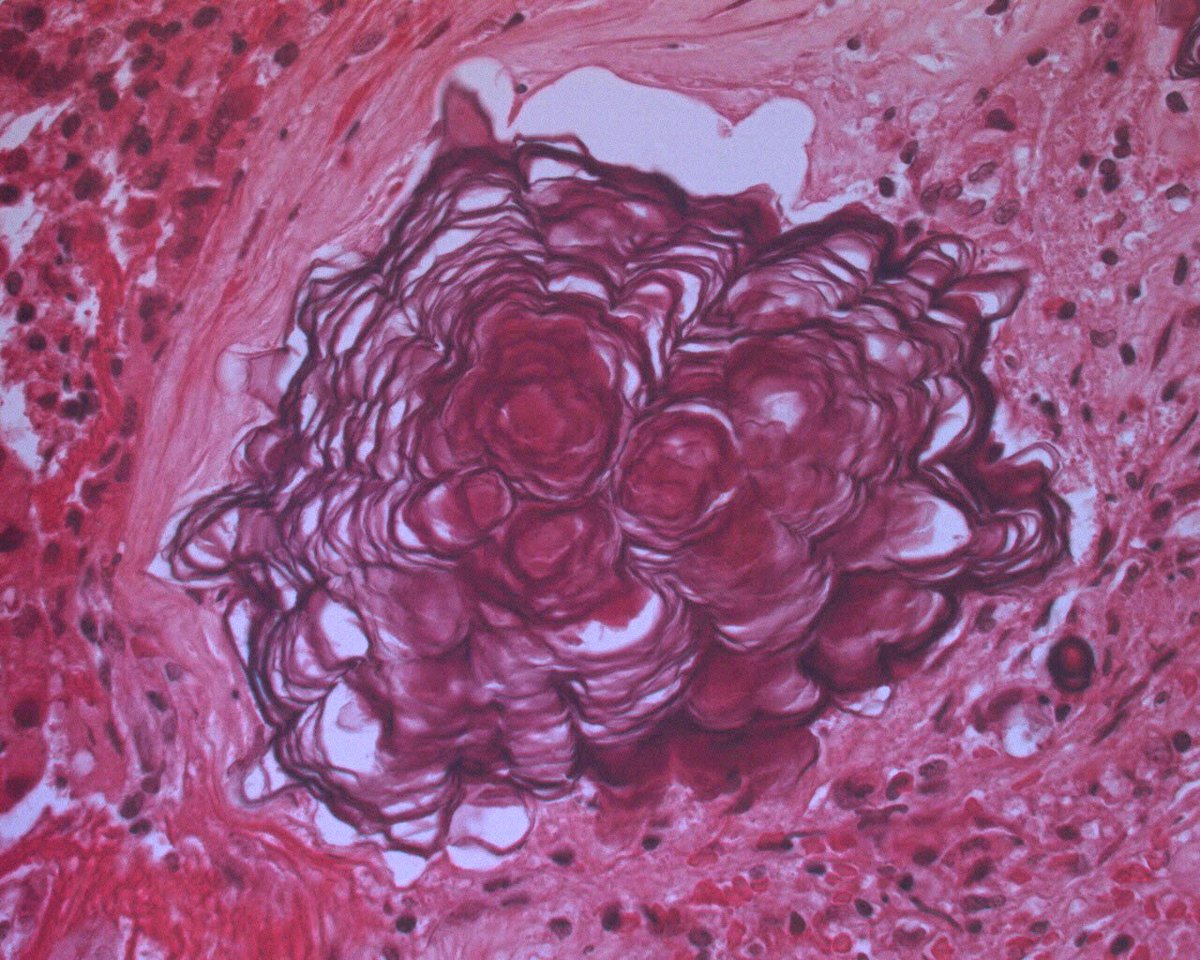

A 60-year-old lady with a 20-year-history of a "brain tumor". She finally decided to have this intraventricular tumor resected because of obstructive hydrocephalus. ¿what is your diagnosis?

#neuropathology#brain#pathologypic.twitter.com/XLyyhPnvEs